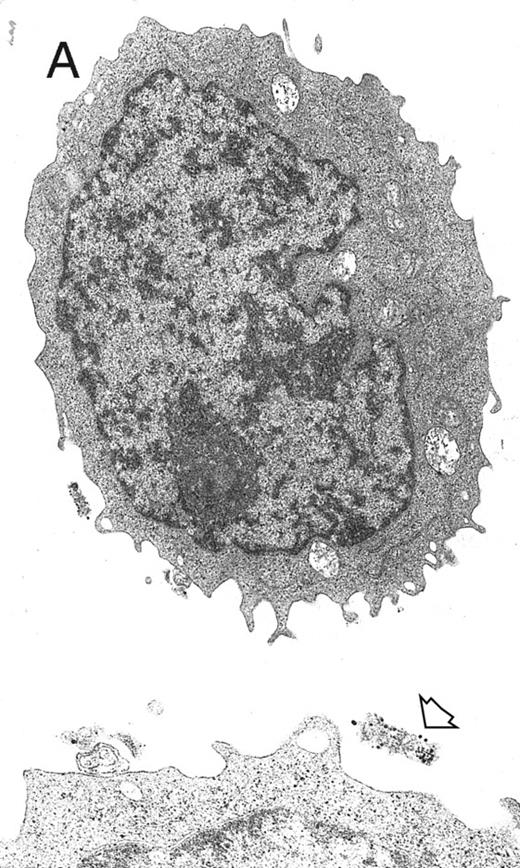

Electron microscopy evaluation of MP generated from purified CD34+ cells cultured for 7 days in the presence of MIP-1α, IL-3, IL-6, IL-11, FL, SCF, and MGDF. In (A) (original magnification × 11,230), an MP cell shows a sparse chromatin, a nucleolus, and few vacuoles and polyribosomes; the cell outline shows some microvilli and few gold particles indicating CD61 labeling (see arrow in the inset; original magnification × 25,120). A significantly more pronounced CD61 labeling is shown in the more differentiated MP in (B) (original magnification × 9,250).